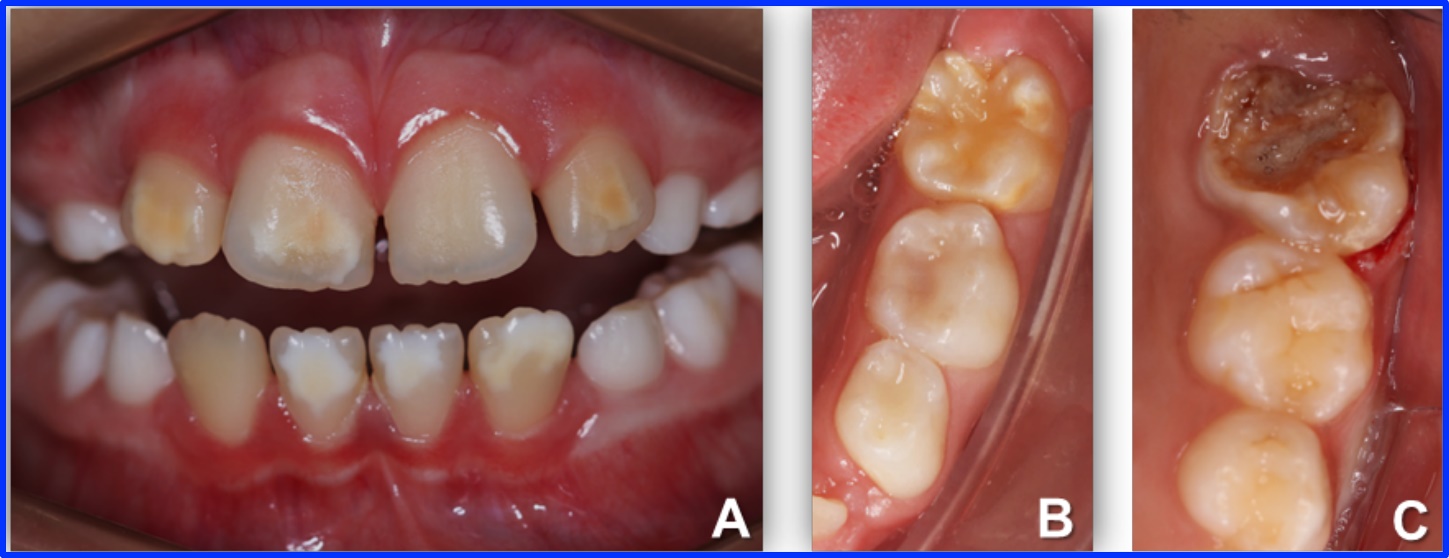

Phục Hồi Mão Thép Làm Sẵn Cho Răng Sữa

Răng sữa đóng vai trò quan trọng trong việc ăn nhai, phát âm và duy trì khoảng trống cho răng vĩnh viễn mọc lên. Tuy nhiên răng sữa có phần men răng và mô ngà...